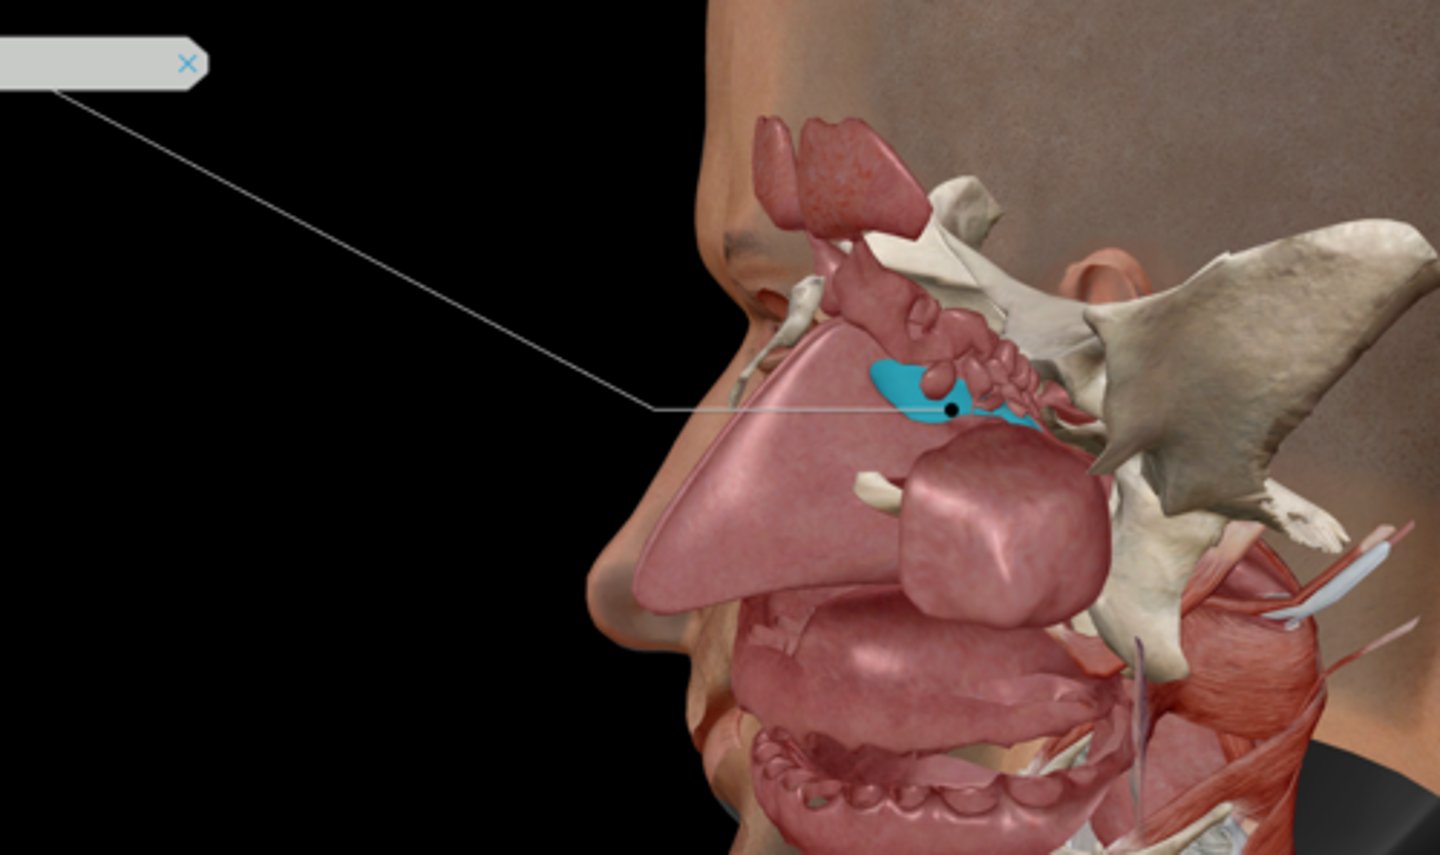

Nasal conchae